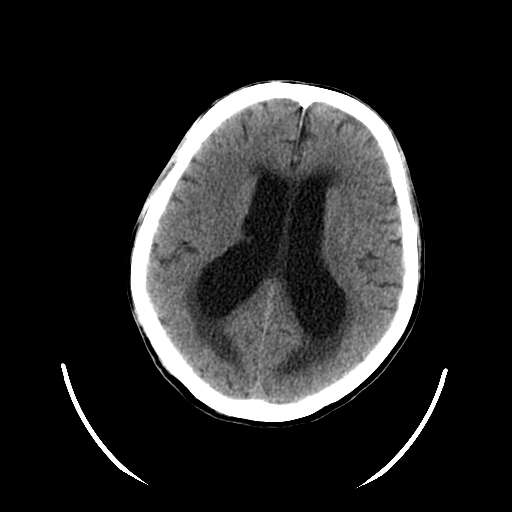

以下是引用hhcckk在2007-10-9 10:03:00的发言:[br]galen';s静脉瘤又称大脑大静脉瘤,是由于动静脉短路,大量血流进入galen';s静脉(大脑大静脉),造成该静脉瘤样扩张所致,病理上典型的galen';s静脉瘤包括一明显扩张的囊状galen';s静脉和引流galen';s静脉的短路血管,,这些短路血管多来源于颈内动脉系统或基底动脉系统,多异常扩大、迂曲。巨大的galen';s静脉瘤可造成中脑压迫,导水管闭塞,引起梗阻性脑积水。[br]galen';s静脉瘤ct表现较典型,根据其部位、形态、增强前后表现及脑积水表现较易诊断。[br]支持张主任,此病人病灶强化明显,正常松果体增强后在病灶的后方可见,可以再做个mr,血管性的病灶在mr上有流空效应,增强后明显强化,诊断更有把握